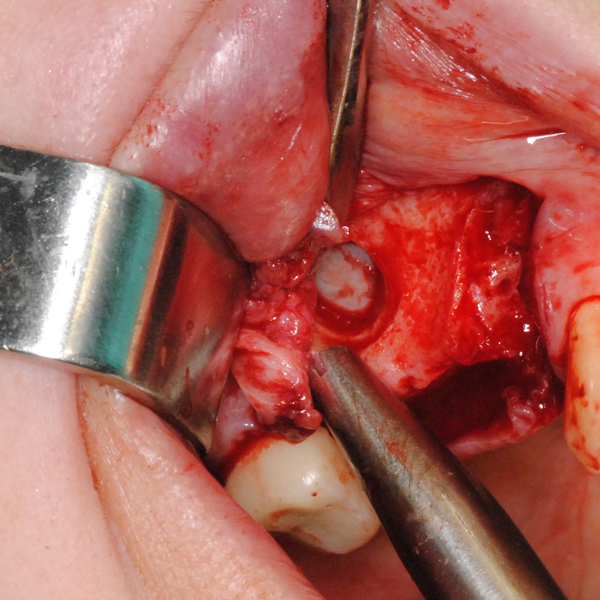

Отворен максиларен синус в началото на интервенцията. Случаят е интересен със следното - твърде атипична форма на трепанационния отвор. На какво се дължи на това - на лошо планиране на оперативния достъп или на нещо друго? Дължи се на факта, че отначало въпросната намеса беше планирана като балонен синуслифт; за съжаление обаче мембраната на синуса се разкъса и надуването на балона стана невъзможно.